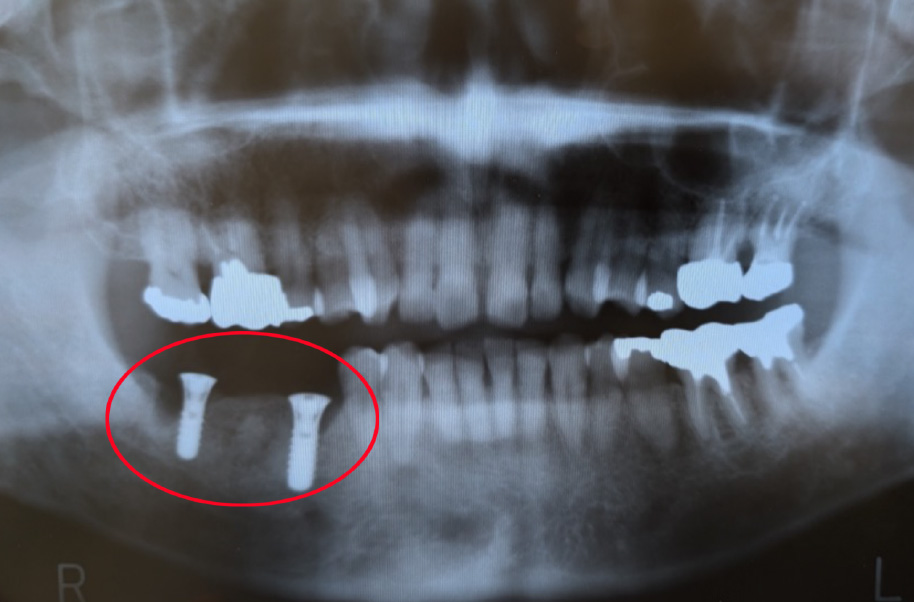

【インプラント埋入直後】2009年6月当時67歳

16年前に右下の奥歯を失い、インプラント治療を受けられた患者様(当時67歳)がいらっしゃいます。

インプラントを2本埋入し、しっかりと噛み合わせを回復させました。